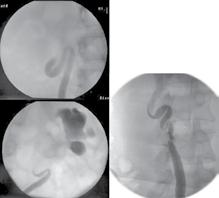

Introducere: Scopul studiului nostru a fost evaluarea retrospectivă a ratei de stone free, după montare de sondă JJ și post-intervenție (ureteroscopie semirigidă, ureteroscopie flexibilă, ureteroscopie semirigidă și flexibilă și NLP) efectuată.

Materiale și metode: Un total de 49 de pacienți care s-au prezentat la camera de garda a Spitalului Clinic de Urgență „Sfântul Ioan” București cu patologie renală acută sugerând prezența unor calculi la nivel renal și/sau ureteral care au fost confirmați prin imagistică (radiografie, ultrasonografie sau tomografie computerizată) au fost incluși în acest studiu retrospectiv, în perioada septembrie 2021 – decembrie 2021. Toți pacienții selectați au avut indicație de intervenție de urgență și au fost tratați prin inserarea unui stent dublu J. Am analizat rata de stone-free după a doua intervenție, care a fost una dintre următoarele: ureteroscopie semirigidă, ureteroscopie flexibilă, ureteroscopie combinată semirigidă și flexibilă și PCNL. Pacienții s-au întors pentru a doua intervenție și au fost reevaluați imagistic.

Rezultate: Procedurile endoscopice au fost efectuate de 4 medici urologi și au fost practicate într-o perioadă de 2 până la 6 săptămâni după procedura inițială de stentare. Stenturile încrustate au fost întâlnite în 4 cazuri și în 5 cazuri pacienții au fost internați cu obstrucția stenturilor introduse anterior. Din totalul de 49 de pacienți, distribuția intervențiilor a fost: 28 cazuri ureteroscopie semirigidă cu o rată stone-free de 19 cazuri; 12 cazuri de ureteroscopie flexibilă cu o rată

a stone-free de 10 cazuri; 5 cazuri cu ureteroscopie combinată flexibilă și semirigidă, cu o rată de stone-free de 4 cazuri; 4 cazuri cu NLP cu o rată de stone-free de 3 cazuri. Rata totală de stone-free pentru toate procedurile a fost de 93.2% Timpul operator mediu a fost de 23 min. Nu au avut loc incidente sau complicații majore în timpul procedurilor.

În studiul nostru am analizat pacienții care după prezentarea la urgență au fost internați și li s-a introdus un stent JJ cu scopul de a pregăti pacientul pentru a doua intervenție care a fost una dintre următoarele: ureteroscopie semirigidă, ureteroscopie flexibilă, ureteroscopie semirigidă și flexibilă și PCNL. Scopul a fost analizarea ratei stone-free după a doua intervenție.

ureteroscopie flexibilă, ureteroscopie combinată semirigidă și flexibilă și NLP. Pacienții s-au întors pentru a doua intervenție și au fost reevaluați imagistic. Toți pacienții selectați au avut indicații de intervenție de urgență și au fost tratați ca prima intervenție de urgență cu inserarea unui stent dublu J. Am analizat rata de stone-free după a doua intervenție care a fost una dintre următoarele intervenții: ureteroscopie semirigidă (Grup A), ureteroscopie flexibilă (Grup B), ureteroscopie combinată semirigidă și flexibilă (Grup C) și NLP (Grup D).

Rezultate

Stenturile încrustate au fost întâlnite în 4 cazuri și în 5 cazuri pacienții au fost internați cu obstrucția stenturilor introduse anterior. Din totalul de 49 de pacienți, distribuția intervențiilor a fost: 28 cazuri ureteroscopie semirigidă cu o rată stone-free de 19 cazuri; 12 cazuri de ureteroscopie flexibilă cu o rată a stone free de 10 cazuri; 5 cazuri cu ureteroscopie combinată flexibilă și semirigidă, cu o rată de stone-free de 4 cazuri; 4 cazuri cu NLP cu o rată de stone-free de 3 cazuri. Rata totală de stone-free pentru toate procedurile a fost de 93.2% Timpul operator mediu a fost de 23 min (Fig. 3).